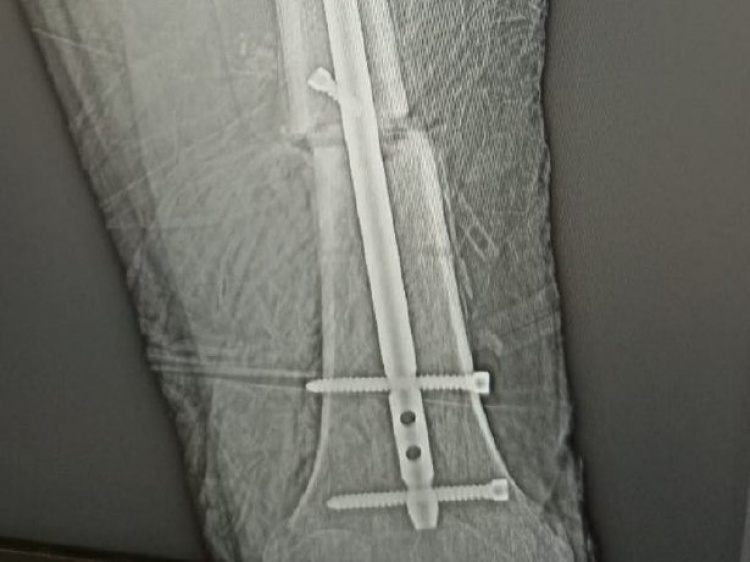

Парень дважды за 4 месяца попал в руки медиков практически с одинаковыми травмами после ДТП . Как сообщили Волжский.ру в облздраве, в марте этого года подросток попал на операционный стол с раздробленной верхней третью левой большой берцовой кости. Хирурги провели высокотехнологичную операцию методом блокируемого интрамедуллярного остеосинтеза . При такой операции в кострномозговой канал вводится стальной или титановый стержень, на который собираются отломки кости. Такой метод позволяет пациенту вернуть подвижность за несколько дней.

Парня удалось благополучно поставить на ноги. Однако неугомонный мотоциклист в июле снова попал на стол к хирургам-травматологам со сложным переломом той же самой ноги. Только в этот раз бедро было сломано в нижней трети. Причем кость сломалась вместе со спицей, которая была в нее установлена ранее. В этот раз парню потребовалась еще более сложная операция и более массивная конструкция, на которую по частям собирали кость.